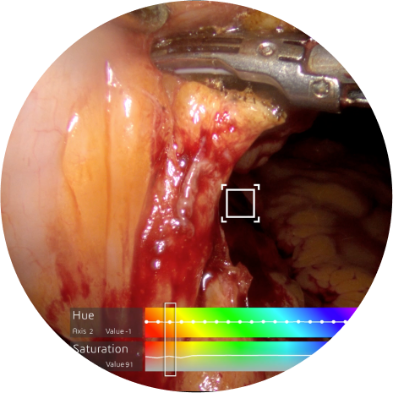

24-Axis Color Adjustment